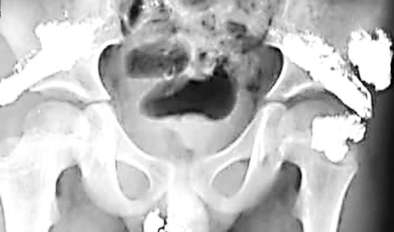

這些“亮晶晶”的東西讓于先生感到很奇怪,為了查明原因,2月5日,于先生帶希希來到昆明醫科大學第一附屬醫院檢查。據X光片檢查結果顯示,希希體內含有大量金屬物質,經醫院診斷,這些金屬是汞,也就是俗稱的水銀。

希希體內存在的水銀,分布在臀部很多位置,且數量驚人。一位護士告訴于先生,希希臀部的水銀量,“最起碼有百八十只溫度計中的水銀含量”。

雖然醫院查出了病因,但由于孩子體內水銀含量太大,考慮到手術取出很可能會導致水銀流向傷口,造成嚴重感染,醫院方面一直沒有做出合適的應對方案。